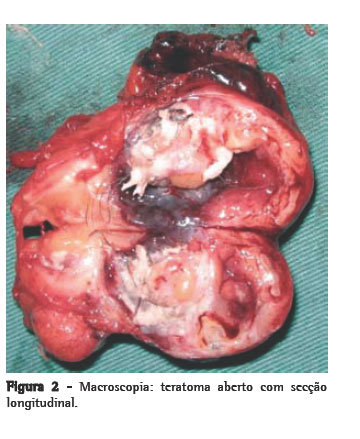

O paciente foi submetido à toracotomia póstero-lateral direita. No intra-operatório, encontramos um tumor de consistência cística e cor amarela, medindo 5,0 × 3,5 × 3,0 cm e pesando 35 g, com áreas de calcificação e localizado no mediastino anterior, sobre a face anterior da veia cava superior, infiltrando o pericárdio e o segmento anterior do lobo superior direito. Iniciou-se dissecção através da abertura da pleura mediastinal, sendo necessárias também ressecção parcial do pericárdio e segmentectomia pulmonar. O mediastino estava livre de linfonodomegalias. O paciente evoluiu sem intercorrências no pós-operatório. Foram encontrados pêlos e secreção sebácea no interior do tumor à abertura da peça (Figura 2). O exame microscópico revelou neoplasia embrionária caracterizada por proliferação de estruturas císticas, ora revestidas por epiderme com glândulas sebáceas e folículos pilosos, ora revestidas por epitélio cilíndrico ciliado de padrão respiratório. Observavam-se feixes musculares lisos, tecido adiposo disposto em lóbulos, agregados linfóides e tecido cartilaginoso. Em certas áreas, havia proliferação de células com núcleos regulares, com cromatina em sal-e-pimenta. Essas células formavam blocos irregulares e apresentavam-se positivas para cromogranina à imunohistoquímica, o que resultou no diagnóstico de teratoma cístico do mediastino com degeneração maligna para tumor carcinóide (Figura 3).

Histologicamente caracteriza-se por apresentar áreas císticas e sólidas. Pode conter dentes, pele e pêlo (folheto ectoderma); cartilagem e osso (folheto mesodérmico); e tecido brônquico, intestinal ou pancreático (folheto endodérmico).(5,8) No caso aqui relatado, foram encontrados tecidos cartilaginoso, epidérmico e ósseo, e também pêlos.